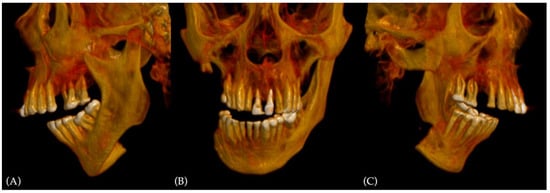

In his past clinical history, the patient was submitted to several reconstruction surgeries after ablative surgery of head and neck squamous cell carcinoma (HNSCC) of the mandibular trigone. The first surgery was tumor resection with TMJ-sparing partial hemimandibulectomy, associated with elective neck dissection (levels I-III) and primary reconstruction with the left fibula free flap. The pathologic staging was pTNM T4N0M0. After surgery, in March 2018, the patient was submitted to RT for two months, with 60 Grays (Gy) on the surgical site and more than 40 Gy on the right lymph nodes. A cause of osteoradionecrosis developed in the mandibular area around the resection, a surgical debridement of the fibula flap was required one month later. Further clinical evaluation revealed parotitis owing to RT and exposed mandibular bone spikes. Parotidectomy and mandibular osteotomy with total free flap removal were carried out, followed by reconstruction with osteosynthesis plate. A new local infection was established, and the patient was re-operated in 2019 for purulent material debridement an osteosynthesis plate removal, leaving a huge bone defect (Figure 3).

Figure 3. Preoperative 3D CT scan reconstruction showing preoperative malocclusion and the bone defect: (A) left-side view; (B) coronal view, with severe deviation to the right side; (C) right-side view, displaying the amount of bone missing from the different previous surgery.